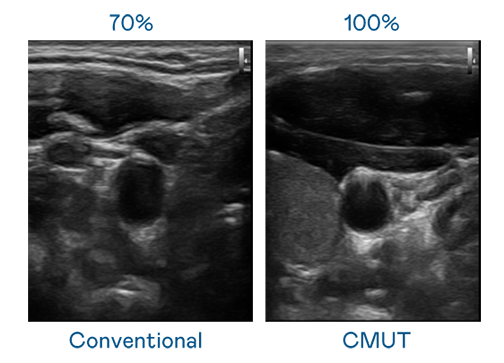

CMUT 技术是一种用电容式微机电元件来产生超音波讯号的技术。与传统 PZT 压电式技术相比,CMUT 频宽增加 30%,更宽频的超音波讯号让影像解析度大幅提升,是实现高影像品质医疗超音波扫描、促进精准医疗发展的关键技术。

大频宽带来超清晰影像

超音波影像的解析度高低,首先取决于探头能发出的讯号频宽。NLC电子 CMUT 可提供高清晰的超音波讯号,提供高频宽、高灵敏度、影像纹理细节更高的超音波影像,协助医护人员缩短影像判读时间及利用精准的医疗影像进行诊断。